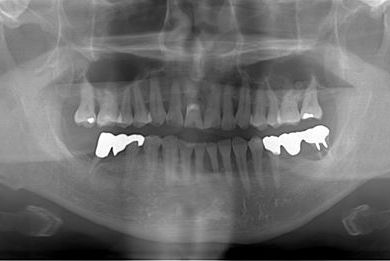

抜歯即日スピードインプラント治療+セラミック治療+歯肉遊離移植術

| 主訴 | 左最奥の下部ブリッジが不安定になっており、奥2本のインプラントを考えたい。 | ||||||||||||||||||||||||||||||||

| 治療方針 | 抜歯と同時にインプラント埋入を行い、治療期間を短縮する。 | ||||||||||||||||||||||||||||||||

| 治療内容 | インプラント4本(抜歯即日スピードインプラント)、メタルボンドセラミッククラウン5本、ハイブリッドセラミッククラウン1本(ハイブリッドセラミック用土台1本) | ||||||||||||||||||||||||||||||||

| 治療期間 | 1年2ヶ月 |